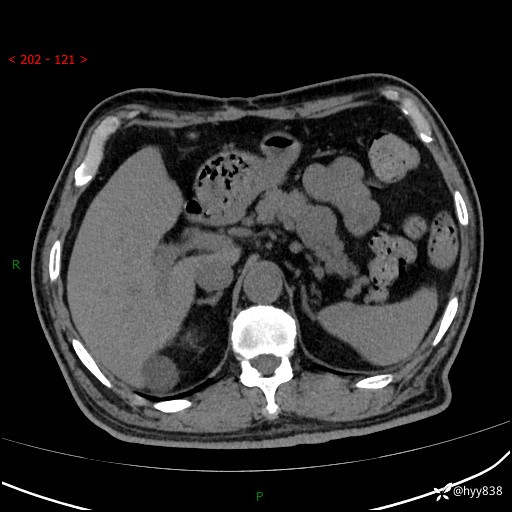

69岁/男,四肢无力3月余。胰腺囊实性占位,渐进性强化---结果公布~

【患者信息】:69岁/男

【主诉】:四肢无力3月余。

【现病史及既往史】:患者3月前无明显诱因出现四肢乏力,伴有口干、多饮、多尿等症状,无畏寒、发热、恶心、腹痛、腹泻等其他症状,于2024-06-13来我院住院治疗,完善相关辅助检查后,考虑“2型糖尿病”,予以降糖(阿卡波糖片 50mg po tid、德谷门冬双胰岛素注射液 8iu 早餐前 皮下注射)等治疗,口干、多饮、多尿较前缓解,血糖控制可;现仍存在四肢乏力,于2024-08-28来我院门诊就诊,查血钾2.88 mmol/L ,现以“低钾血症”收入我科。 本次起病以来,患者精神、饮食、睡眠良好,二便正常,近3月余体重下降约5kg。

【检查】:胰腺CT平扫+增强